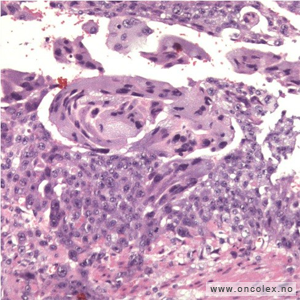

Bildeeksempler: Epitelial eggstokkreft

Lysmikroskopibilde av serøst papillært karsinom i egglederen.

Svulster i egglederen likner på de som ses i eggstokkene. For å klassifisere en svulst i egglederen som en primærtumor må den kun være på egglederen. Det skal ikke være svulstvev i eggstokk eller livmor. Hvis det er svulst i livmor, må det være av en annen type, eller det må klart dreie seg om en spredning.

Mikroskopisk er den serøse typen mest vanlig. De mindre vanlige svulsttypene er de endometrioide (likner livmorslimhinne), mucinøse (slimete), klarcellete, av overgangsepiteltype og de udifferensierte. Svulster med blandete epiteliale (overflatevev) og mesenkymale (støttevev) komponenter, for eksempel karsinosarkom, ses også en sjelden gang med utløp i egglederen.